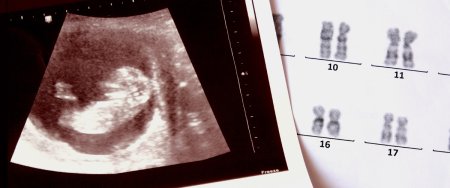

Daun Sindromu Nədir?